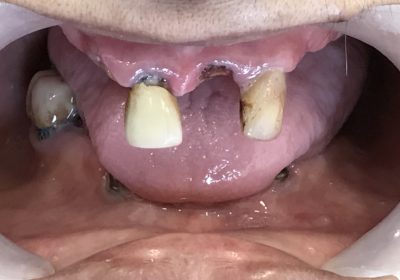

Full mouth rehabilitation with dental implants is a comprehensive dental procedure designed to restore the entire mouth's function, aesthetics, and health by using dental implants as the primary treatment modality. This treatment approach is typically reserved for individuals with extensive dental problems, including multiple missing teeth, severe tooth decay, advanced gum disease, or a combination of these issues. Full mouth rehabilitation with dental implants aims to provide a long-lasting, stable, and natural-looking solution for such patients. Here's an overview of what this procedure entails: 1. **Assessment and Planning**: The process begins with a thorough assessment of the patient's oral health. X-rays, scans, and clinical examinations are conducted to determine the extent of dental issues and the suitability of dental implants. A detailed treatment plan is then created, outlining the number of implants required and the type of dental restorations needed. 2. **Implant Placement**: Dental implants, which are artificial tooth roots typically made of biocompatible materials like titanium, are surgically placed into the jawbone. The number of implants and their precise locations depend on the patient's individual case. Local anesthesia is used during this procedure, and sedation options may be available for anxious patients. 3. **Healing and Osseointegration**: After implant placement, a crucial healing period follows. During this time, which can last several months, the dental implants integrate with the surrounding bone through a process called osseointegration. This fusion ensures the implants are securely anchored in the jawbone, providing a stable foundation for the prosthetic teeth. 4. **Abutment Placement**: Once osseointegration is complete, small connector pieces called abutments are attached to the implant posts. These abutments serve as a link between the dental implants and the final restorations. 5. **Final Restorations**: After the gum tissues have healed around the abutments, custom-made dental restorations (such as crowns, bridges, or dentures) are fabricated. These restorations are designed to mimic the appearance and function of natural teeth, and they are securely attached to the abutments. 6. **Ongoing Maintenance**: Proper oral hygiene and regular dental check-ups are crucial for the long-term success of full mouth rehabilitation with dental implants. Patients are typically provided with guidance on how to care for their new teeth, and they should follow a strict maintenance routine to ensure the longevity of their dental implants. Advantages of Full Mouth Rehabilitation with Dental Implants: 1. **Improved Functionality**: Dental implants offer stability and strength, enabling patients to eat, speak, and chew with confidence, similar to natural teeth. 2. **Enhanced Aesthetics**: The restorations used in this procedure are customized to look and feel like natural teeth, significantly improving the appearance of the smile. 3. **Long-Term Solution**: With proper care, dental implants can last for many years, often a lifetime, making them a cost-effective option in the long run. 4. **Preservation of Jawbone**: Implants stimulate the jawbone, preventing bone loss and maintaining facial structure over time, which is a common concern with traditional dentures. 5. **Comfort and Convenience**: Unlike removable dentures, dental implants are fixed in the mouth, eliminating discomfort and inconvenience associated with removable prosthetics. 6. **Improved Oral Health**: Full mouth rehabilitation can enhance oral health by preventing the shifting of remaining natural teeth and reducing the risk of gum disease. In summary, full mouth rehabilitation with dental implants is a transformative dental procedure that provides patients with a functional, aesthetically pleasing, and long-lasting solution for complex dental issues involving multiple missing teeth or extensive dental damage. It combines advanced surgical techniques with customized dental restorations to create a healthy, confident smile. A patient reports for replacement of a few missing teeth. On Examination it was found : 1]Posterior teeth were fractured and missing. 2]Anterior teeth were mobile. 3]Patient was chewing only with the front teeth. A thorough examination was done with Extra Oral Photographs, Intra Oral Photographs, CBCT Scan, 3D Scan with 3 Shape Scanner.OPG Scan, Various measurements like Vertical Dimensions, Smile Line, etc. A treatment plan was devised based on the principles of DSD[ Digital Smile Designing]. Digital technology was used to determine the final positions and look of Smile before actually doing it in the patient mouth. The surgery was done in just 2 visits, one for each jaw.[UPPER & LOWER]